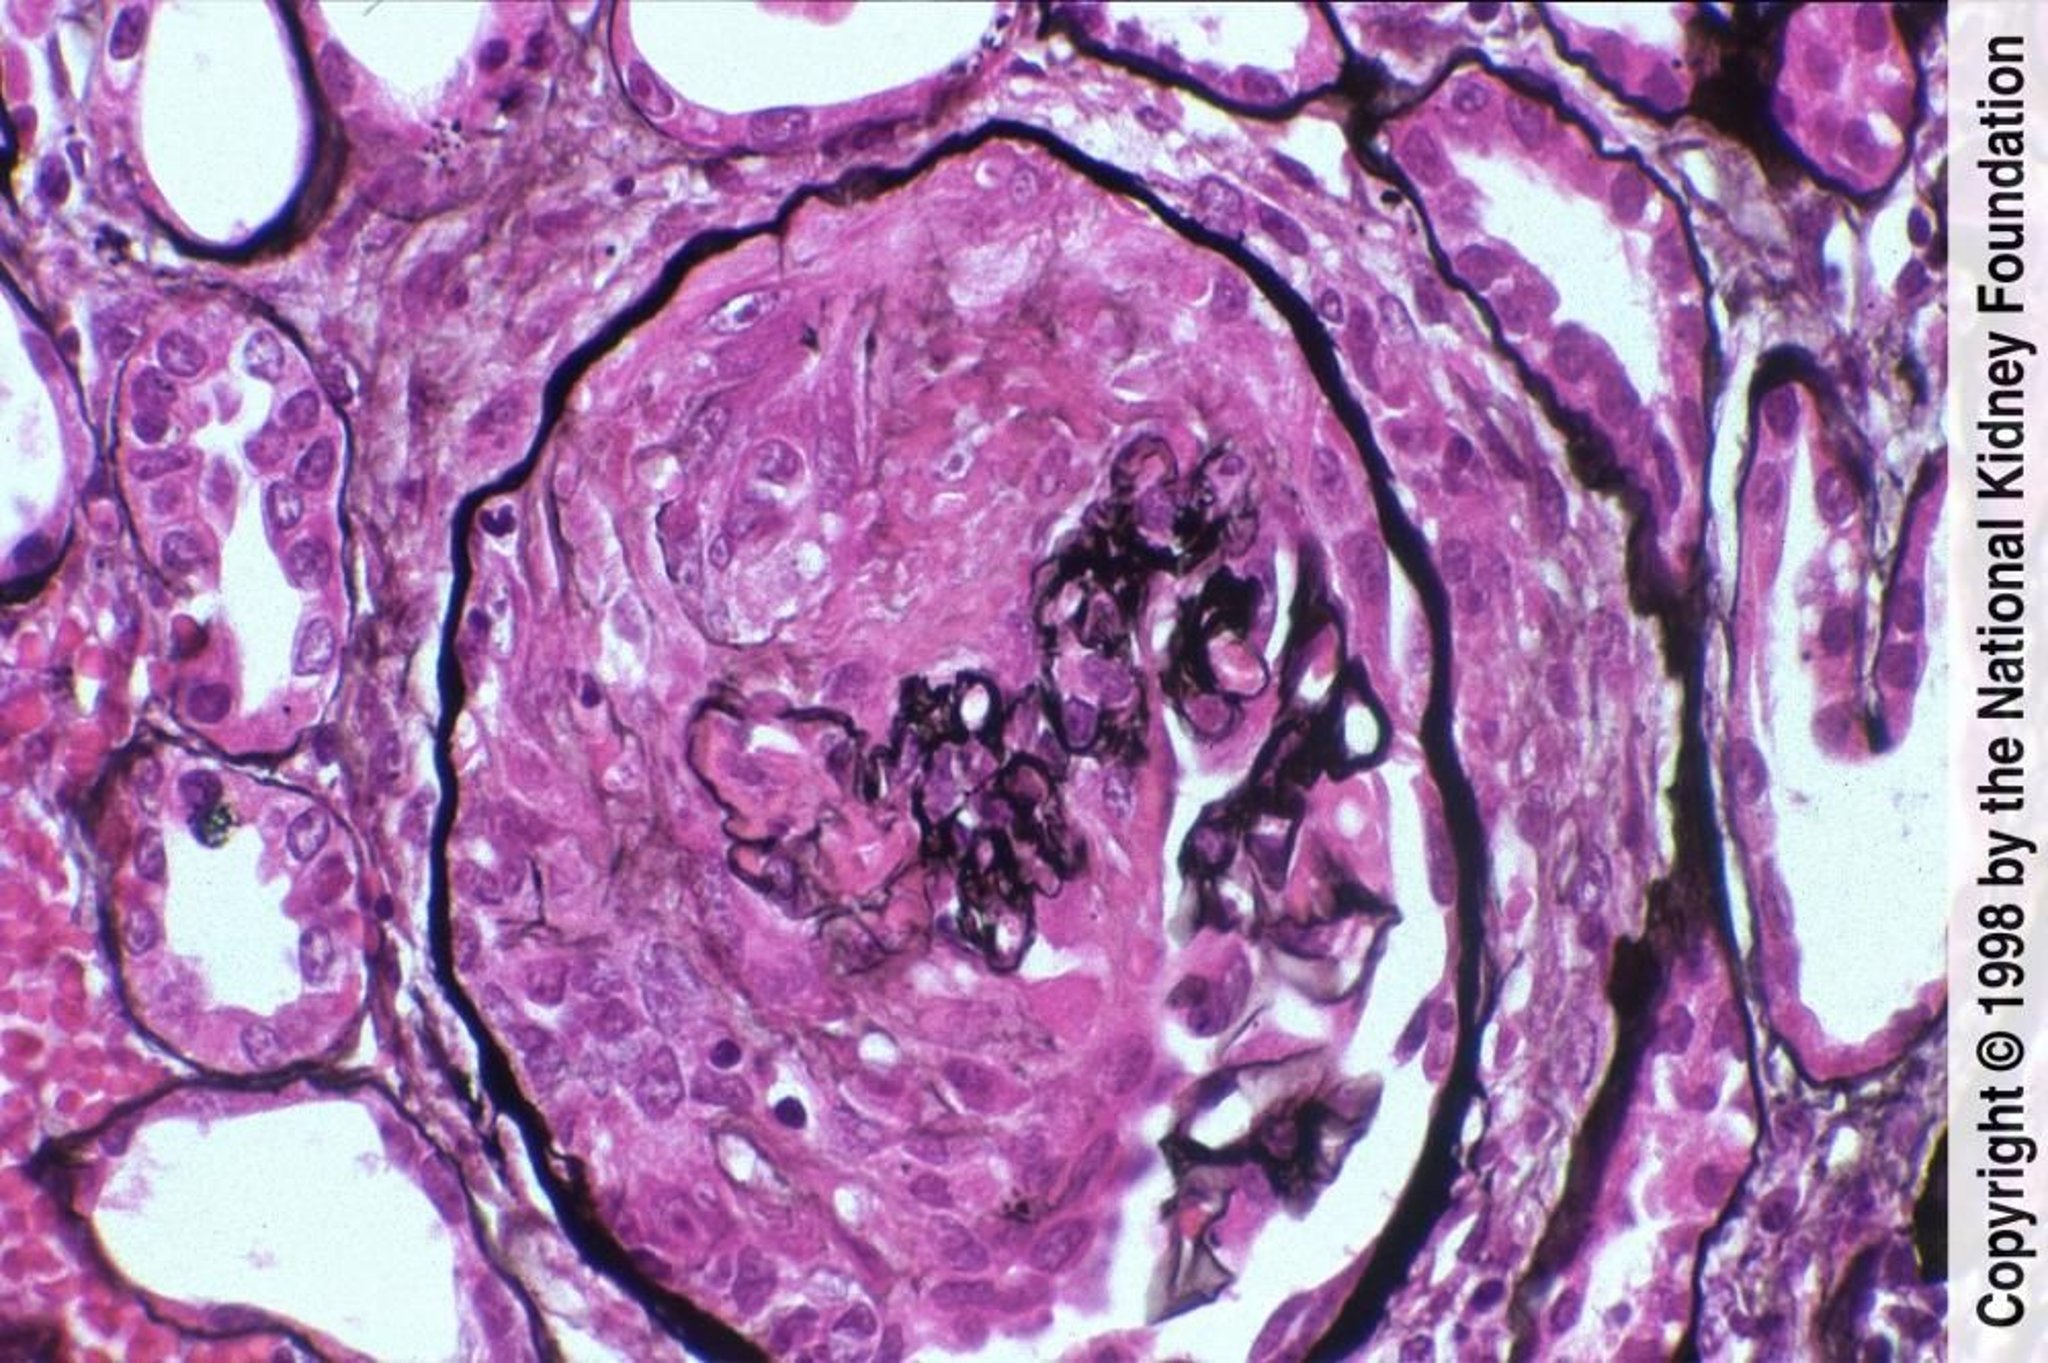

Glomérulonéphrite rapidement progressive (Pauci-Immune)

La maladie pauci-immunitaire est caractérisée par la formation de croissants avec nécrose fibrinoïde et coloration par immunofluorescence négative (coloration de Jones à l'argent, ×400).

Image provided by Agnes Fogo, MD, and the American Journal of Kidney Diseases' Atlas of Renal Pathology (see www.ajkd.org).